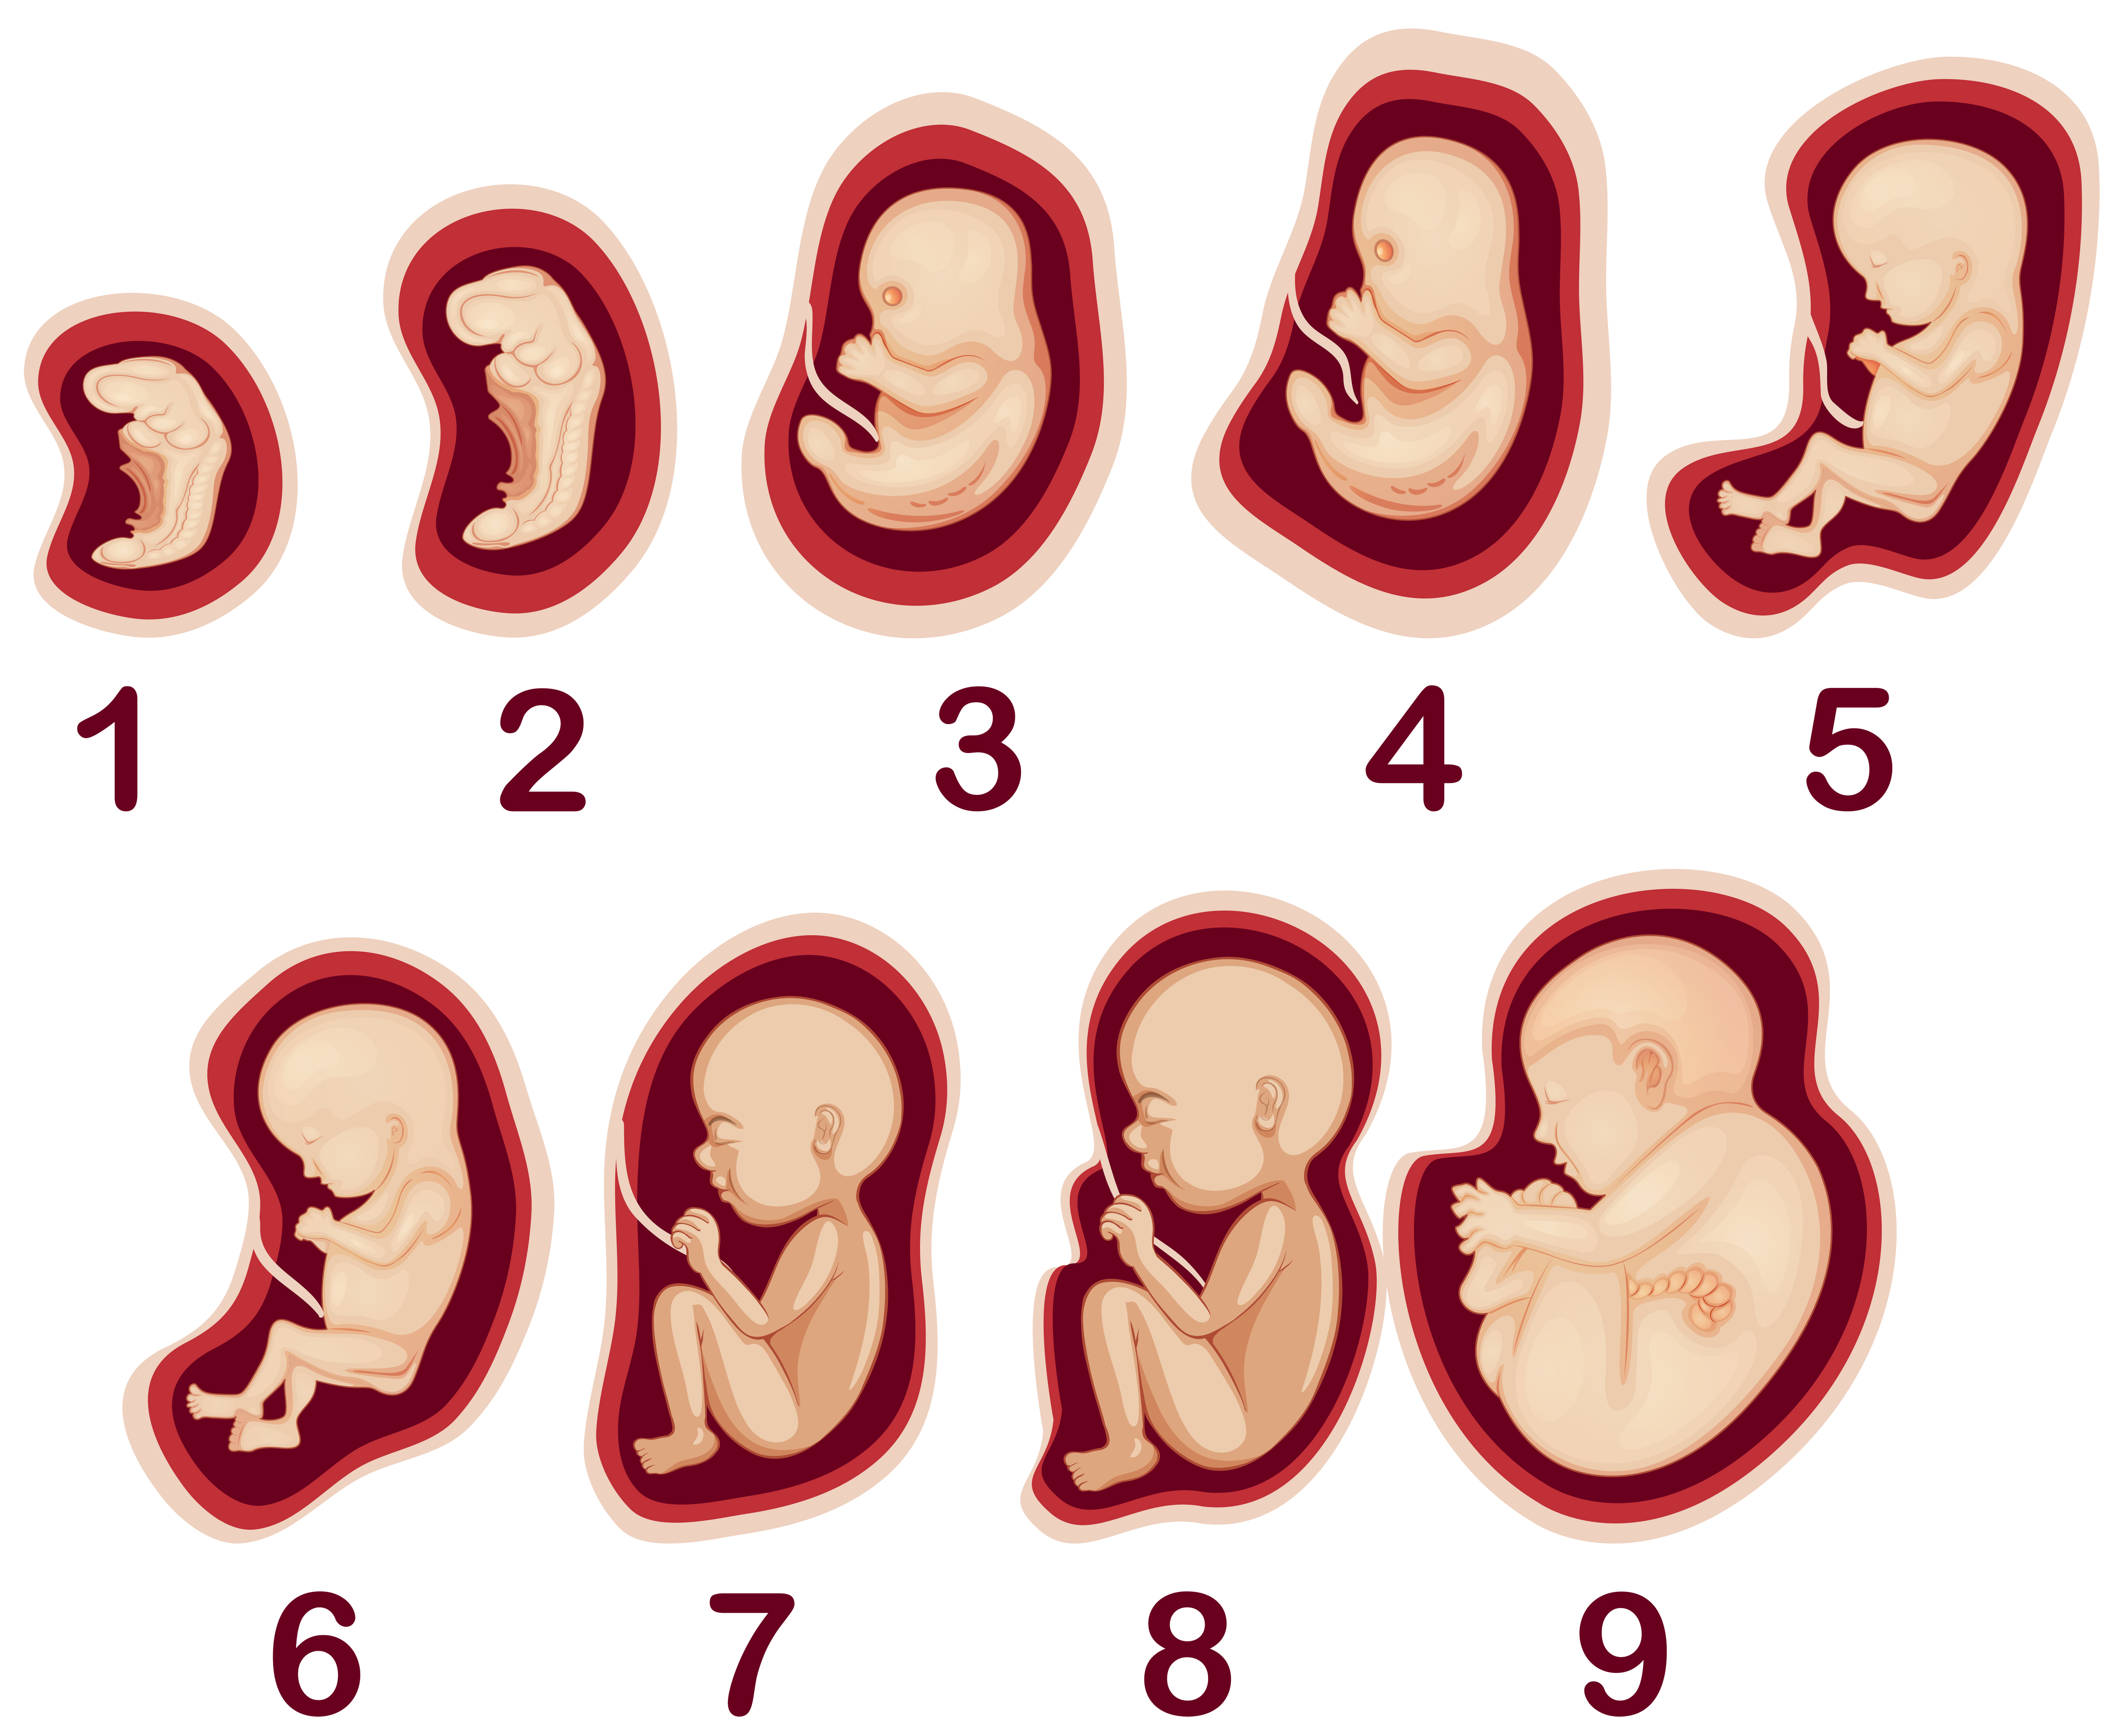

Фотография Плода В Животе

Фотография Плода В Животе 113 фотографий